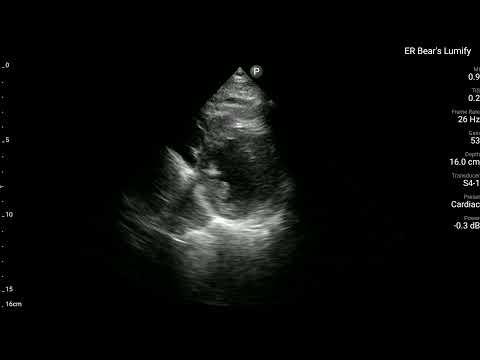

當時我用了自己Lumify做了Echo,大家會希望在哪個地方看出什麼問題呢?

所以我們在ECG看到懷疑是Post.wall MI,當然我們超音波的目光就要放到Post.wall的附近(Segment 4、5、10、11都要看),是否有明顯RWMA。如果有,那麼超音波的發現就和ECG的發現完全吻合,就更可證明這確實就是Post.wall MI。

看Fig.5左側,可以知道A4C其實不容易看到Post.wall。A2C與PSAX可以看到。

- PSAX是看縱切面,可以看到Segment 4、5、10、11

PSAX是最佳可以看到Post.wall與其附近RWMA的最好view。

回頭看看上面的POCUS Clip(PSAX view),把一根手指頭放在LV中間,有沒有發現Segment 4、5附近是不是不太動。

賓果!!!!

POCUS finding is compatible with ECG finding.

Tips:如果懷疑Post.wall MI →PSAX view就最好eyeballing觀看的view